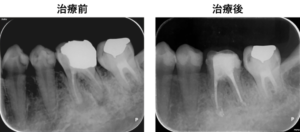

今回は、右下の奥歯の歯の根に炎症があり膿が出ていた歯の根に対して根管治療を行った症例をご紹介いたします。

治療前

左下6番の歯の根の先に炎症があり膿が出ていたので、根の治療(根管治療)を提案し、患者様の合意を頂き治療をすすめることになりました。

左図のレントゲン写真では根の先に炎症があり骨が溶けている部分があります(矢印部) 。

治療後

奥歯は複数の根があり、根の病気になるとなかなか治癒させるのが難しいです。

しかし、精密根管治療でマイクロスコープを用いて、目視下で原因となる根の中の汚れを除去し、抗菌性のある材料で根の中をつめるとこのように治癒に導くことができます。治療に伴い症状が全くなくなったため、患者様はとても喜ばれておられました。